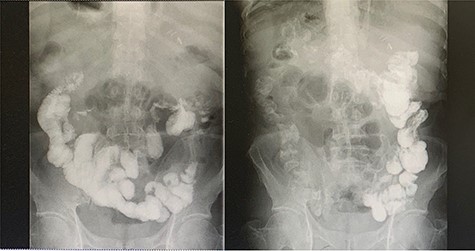

A 52-year-old male had no obvious inducement of epigastric pain for >3 months presenting persistent stabbing pain, accompanied by back pressure, fatigue, loss of appetite and hiccup. He went to a local hospital for treatment because of aggravated abdominal pain. Gastroscopy showed: (i) gastric polyps and (ii) chronic atrophic gastritis. The symptoms were not relieved after oral medication. Two weeks later he had jaundice with clay-like stool, so he went to the local hospital and underwent a color Doppler ultrasound examination. The results showed that: (i) visceral inversion; (ii) solid space-occupying at the head of the pancreas; (iii) dilated inner diameter of the intrahepatic and extrahepatic bile ducts and main pancreatic duct; (iv) fatty liver and (v) enlarged gallbladder volume and wall rough. The patient was admitted to our hospital complaining of ‘epigastric pain >3 months ago, jaundice with clay-like stool for 1 week’. The patient had no significant medical, surgical or drug history. Physical examinations were unremarkable except for a weight loss of ~20 kg since the onset of the disease. Blood and laboratory tests were carried out, and they showed elevated values of liver enzymes, with a clear elevation in the values of Enzyme gamma-glutamyl transferase (GGT) and alkaline phosphatase (ALP), as well as tumor markers CA19-9, CEA and CA72-4, which are indicative of the presence of an obstructive lesion (Table 1). After preoperative examinations, he was diagnosed with pancreatic cancer. His CT scan (Fig. 1) showed: (i) mirror dextrocardia; total visceral inversion; (ii) pancreatic space-occupying lesions; (iii) intrahepatic and extrahepatic bile duct dilation; (iv) intrahepatic calcification and (v) multiple small cysts in the left kidney, and the MRI scan has confirmed the previous results (Fig. 2). A perioperative plan has been made for a LPD. The patient was put under general anesthesia in a supine split–leg position. The laparoscopic instruments were connected (Fig. 3). Diagnostic laparoscopy confirmed a mirror transportation of organs hence confirming SIT, considering the preoperative assessments and intraoperative exploration, a LPD, and intestinal adhesiolysis was performed. Major vessels along with thoracic and abdominal organs were transposed as mirror images of the normal anatomy, a 17-cm paramedian incision in the upper left abdomen was made to accomplish the resection of the organs which includes the distal stomach—the duodenum, the upper segment of the jejunum, the common bile duct and the gallbladder. According to conventional loop reconstruction, the reconstruction of the alimentary tract was performed. Three drainage tubes were placed at the sites of the anastomoses. Although there were anatomical variations, the operation went smoothly. The blood pressure of the patient was stable and the anesthesia effect was satisfactory within 150-ml intraoperative blood loss. The postoperative specimens were sent to the pathological lab. Postoperative fluoroscopy was normal (Fig. 4). The patient had a total hospital stay of 26 days; 15 days postoperative hospital stay, and was discharged without any complications.

Left-image is postoperative fluoroscopy confirming smooth passage of contrast in the remnant stomach and the gastrojejunostomy with no stenosis or flaccidity; Right-image confirming smooth passage of contrast in the choledochojejunostomy and pancreaticojejunostomy.